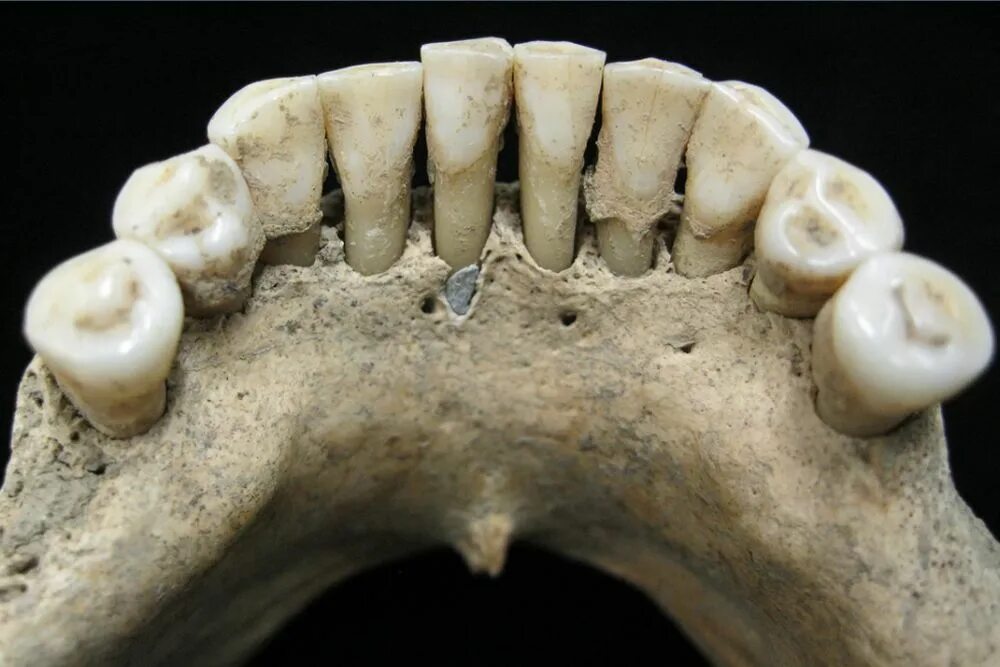

Зубы слева